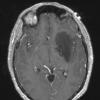

NEOPLASMS (GLIAL)

Astrocytoma, IDH-mutant, WHO Grade 2 (5)